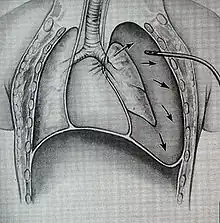

Treatment of TBI varies based on the location and severity of injury and whether the patient is stable or having trouble breathing,[2] but ensuring that the airway is patent so that the patient can breathe is always of paramount importance.[10] Ensuring an open airway and adequate ventilation may be difficult in people with TBI.[3] Intubation, one method to secure the airway, may be used to bypass a disruption in the airway in order to send air to the lungs.[3] If necessary, a tube can be placed into the uninjured bronchus, and a single lung can be ventilated.[3] If there is a penetrating injury to the neck through which air is escaping, the trachea may be intubated through the wound.[10] Multiple unsuccessful attempts at conventional (direct) laryngoscopy may threaten the airway, so alternative techniques to visualize the airway, such as fiberoptic or video laryngoscopy, may be employed to facilitate tracheal intubation.[10] If the upper trachea is injured, an incision can be made in the trachea (tracheotomy) or the cricothyroid membrane (cricothyrotomy, or cricothyroidotomy) in order to ensure an open airway.[6] However, cricothyrotomy may not be useful if the trachea is lacerated below the site of the artificial airway.[10] Tracheotomy is used sparingly because it can cause complications such as infections and narrowing of the trachea and larynx.[26] When it is impossible to establish a sufficient airway, or when complicated surgery must be performed, cardiopulmonary bypass may be used—blood is pumped out of the body, oxygenated by a machine, and pumped back in.[26] If a pneumothorax occurs, a chest tube may be inserted into the pleural cavity to remove the air.[12]